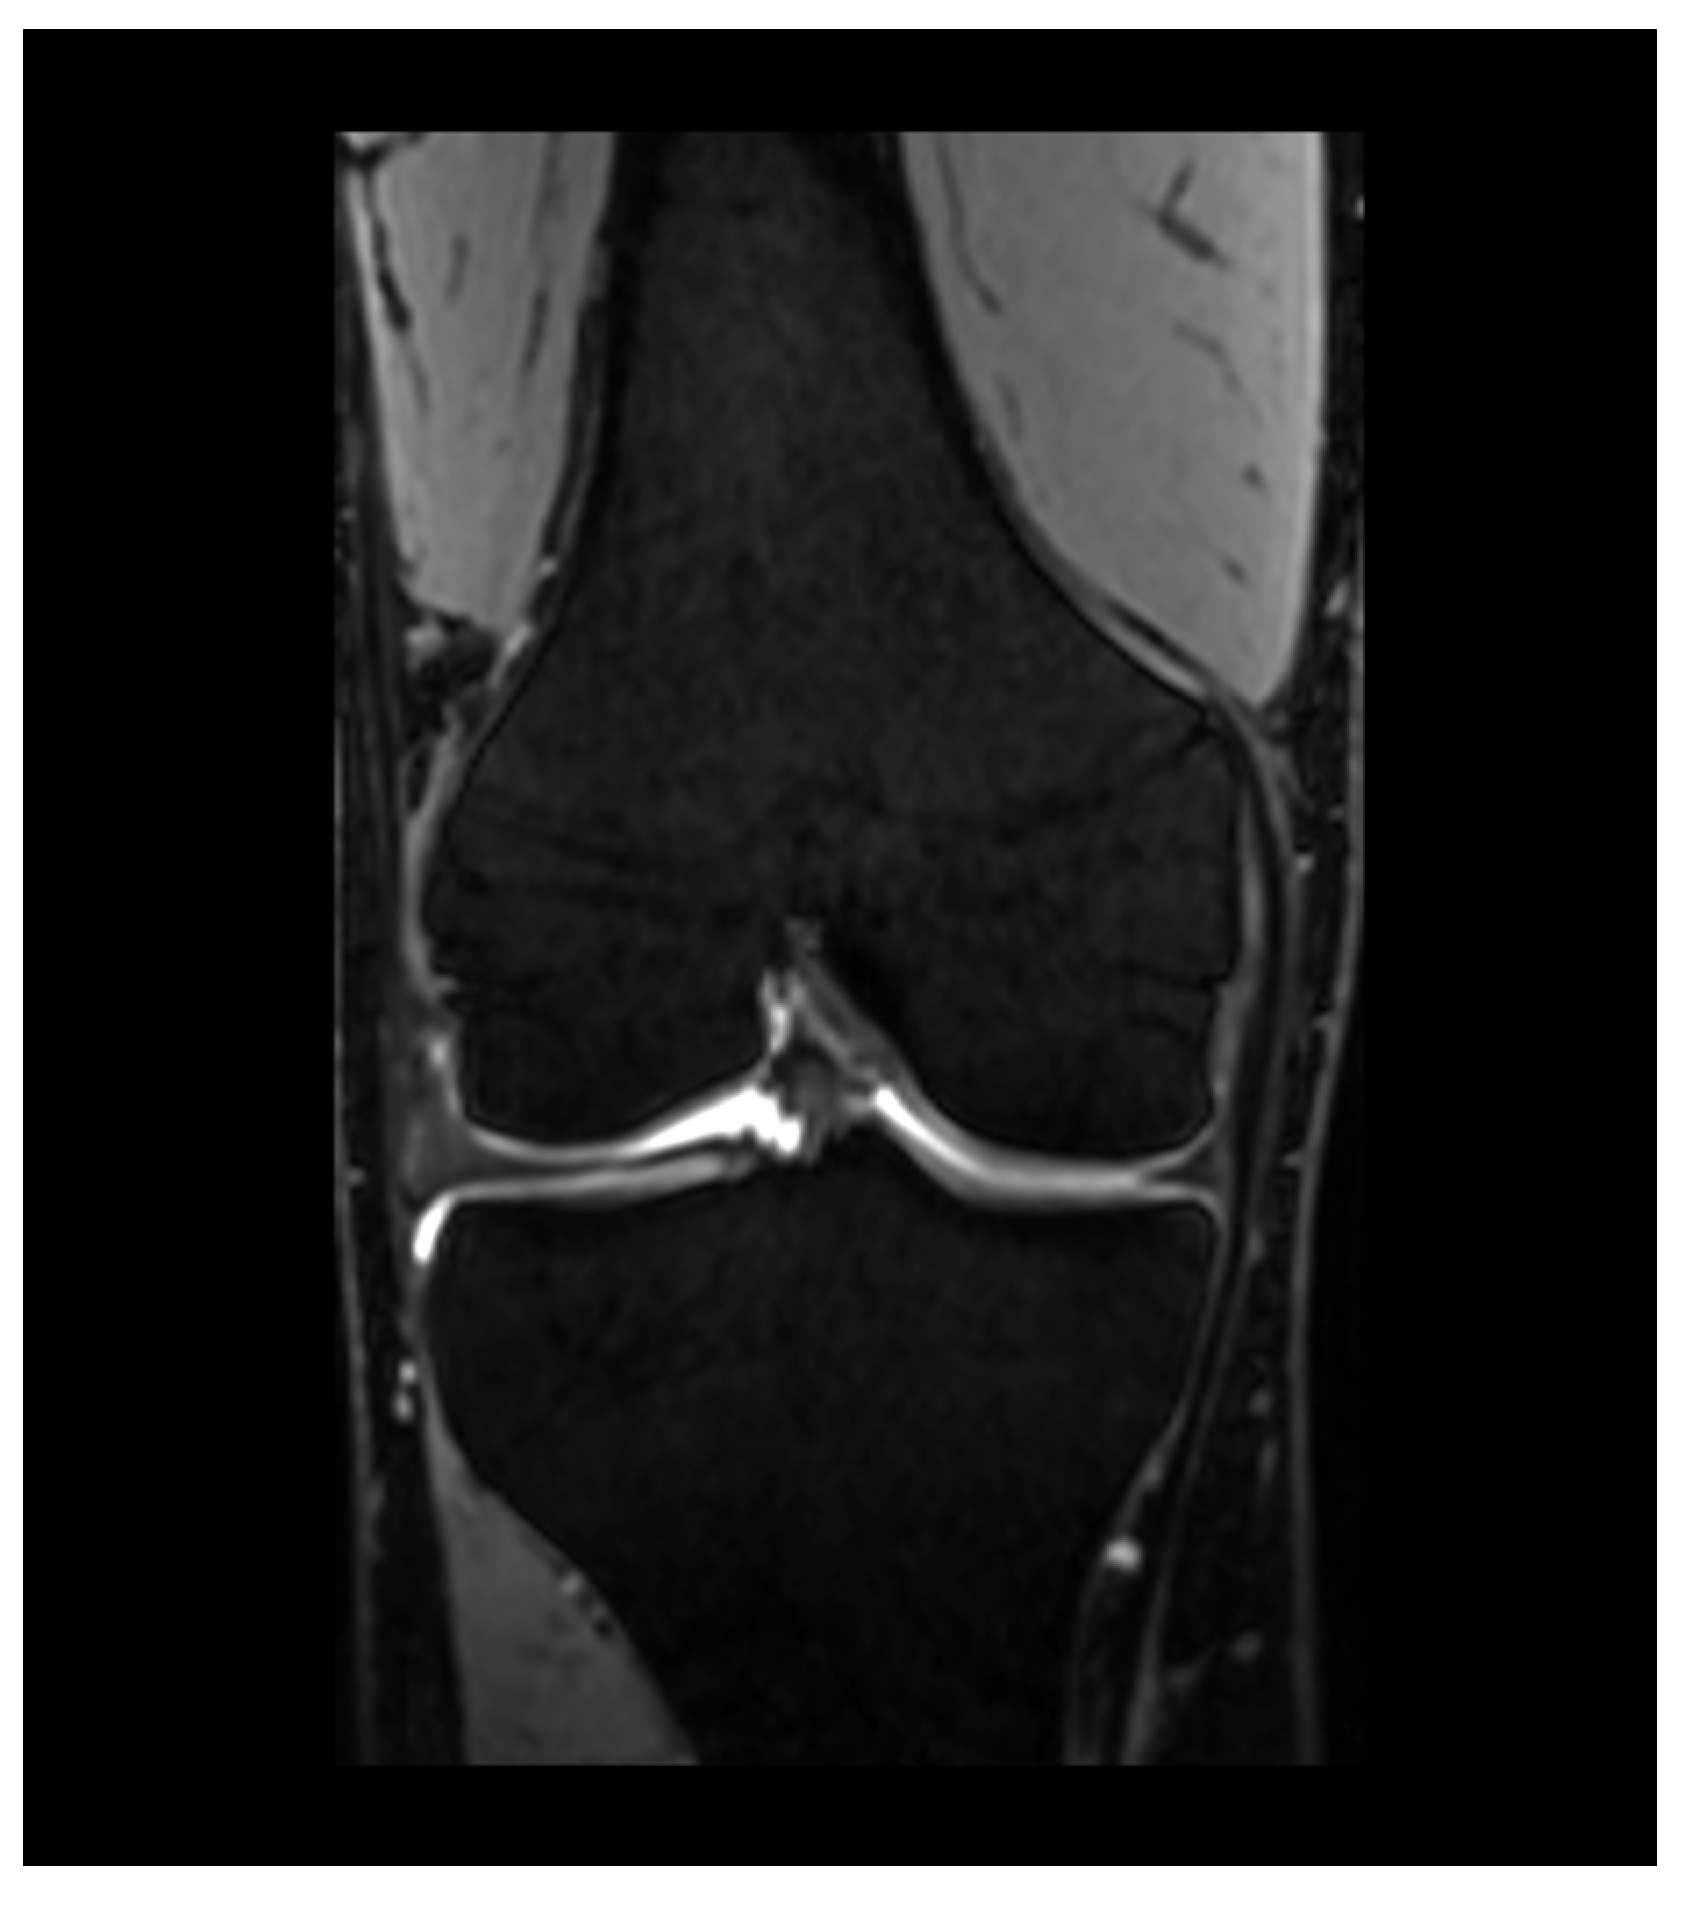

After correct placement of the patient and the receiver coil (Figure 2), the workflow starts with the acquisition of three-plane localizers. Axial images are planned parallel to the knee joint line, while sagittal planes are planned parallel to the medial facet of the lateral condyle. Coronal planes are arranged parallel to the posterior facets of the femoral condyles. A contrast-enhanced T1w FS image may be added as an option if inflammation, such as synovitis or osteitis, or malignancy is suspected. The ESSR (Table 1) recommends a slice thickness of 3 mm for all images. The field of view (FOV) for the PDw images is recommended to be 16 cm with a matrix of 288 × 384. T1w-images should be acquired at an FOV of 18 cm with a matrix of 358 × 512 [38,39].

Figure 2. Patients enter the scanner feet first in a supine position. The coil is placed around the knee and the joints are immobilized with adequate padding.